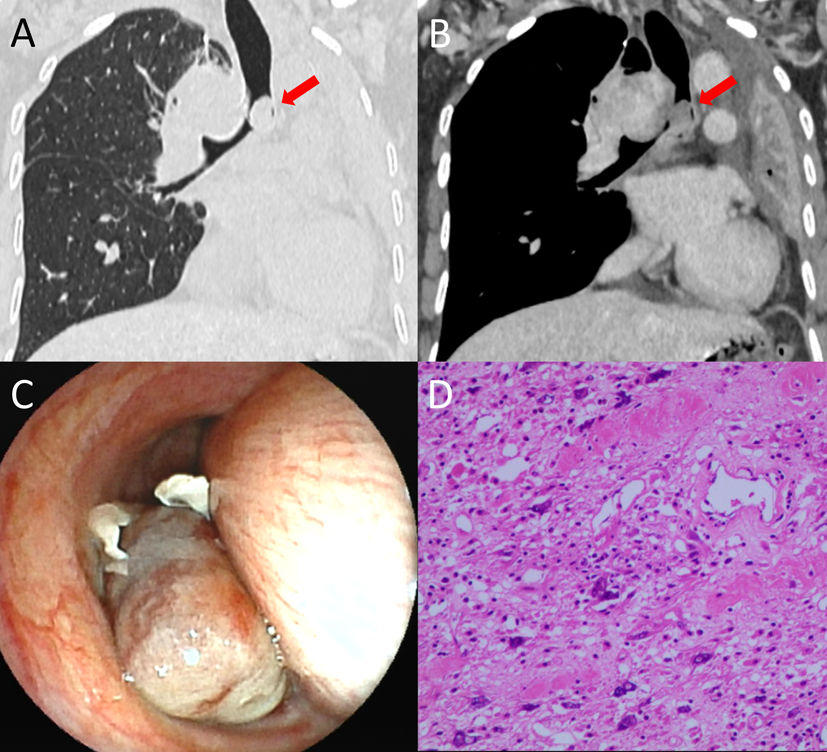

Chest CT (A, B) revealed a nodular soft tissue density (arrows) within the left main bronchus demonstrating mild enhancement after contrast administration. A lobulated soft tissue mass was observed below the carina, showing marked enhancement post-contrast. Bronchoscopy (C) demonstrated complete obstruction of the left main bronchial lumen by a neoplasm and significant extrinsic compression causing stenosis of the right main bronchus. Microscopically (D), heterogeneous cellular density, cellular pleomorphism, nuclear pleomorphism (variation in nuclear size and shape), and abundant cytoplasm were noted.

A 56-year-old female was evaluated due to persistent cough and wheezing lasting over one month. Chest CT (Fig. 1A, B) revealed a nodular soft tissue density lesion, measuring approximately 10mm×14mm, within the left main bronchus, which exhibited mild enhancement post-contrast. Obstructive atelectasis was observed in the left lung. A lobulated soft tissue mass, measuring approximately 43mm×61mm, was identified below the carina and demonstrated marked enhancement post-contrast. Bronchoscopy (Fig. 1C) demonstrated complete obstruction of the left main bronchus by a neoplasm, with significant extrinsic compression causing narrowing of the right main bronchus. Histopathological examination (HE and IHC, Fig. 1D) of the bronchoscopic biopsy specimen revealed findings consistent with liposarcoma. Bronchial liposarcoma is a malignant tumor originating from primitive mesenchymal tissue, specifically adipocyte precursor cells, within the bronchial or tracheal wall. While liposarcoma represents a relatively common subtype of soft tissue sarcoma (approximately 20%), its primary occurrence within the bronchi or trachea is exceptionally rare, constituting an infrequent type of primary endobronchial malignancy [1,2]. It is most frequently diagnosed in adults aged 40–60 years. Clinical manifestations primarily result from bronchial lumen obstruction, with cough being the most common symptom, followed by dyspnea or wheezing secondary to airway narrowing.